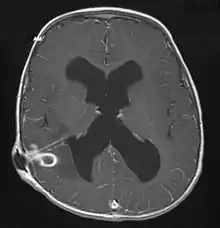

MRI (T1 with contrast) showing the ring-enhancing lesion. From a rare case report of an abscess formed as a complication of the CSF shunt. Jamjoom et al., 2009.[1]

The diagnosis is established by a computed tomography (CT) (with contrast) examination. At the initial phase of the inflammation (which is referred to as cerebritis), the immature lesion does not have a capsule and it may be difficult to distinguish it from other space-occupying lesions or infarcts of the brain. Within 4–5 days the inflammation and the concomitant dead brain tissue are surrounded with a capsule, which gives the lesion the famous ring-enhancing lesion appearance on CT examination with contrast (since intravenously applied contrast material can not pass through the capsule, it is collected around the lesion and looks as a ring surrounding the relatively dark lesion). Lumbar puncture procedure, which is performed in many infectious disorders of the central nervous system is contraindicated in this condition (as it is in all space-occupying lesions of the brain) because removing a certain portion of the cerebrospinal fluid may alter the concrete intracranial pressure balances and causes the brain tissue to move across structures within the skull (brain herniation).